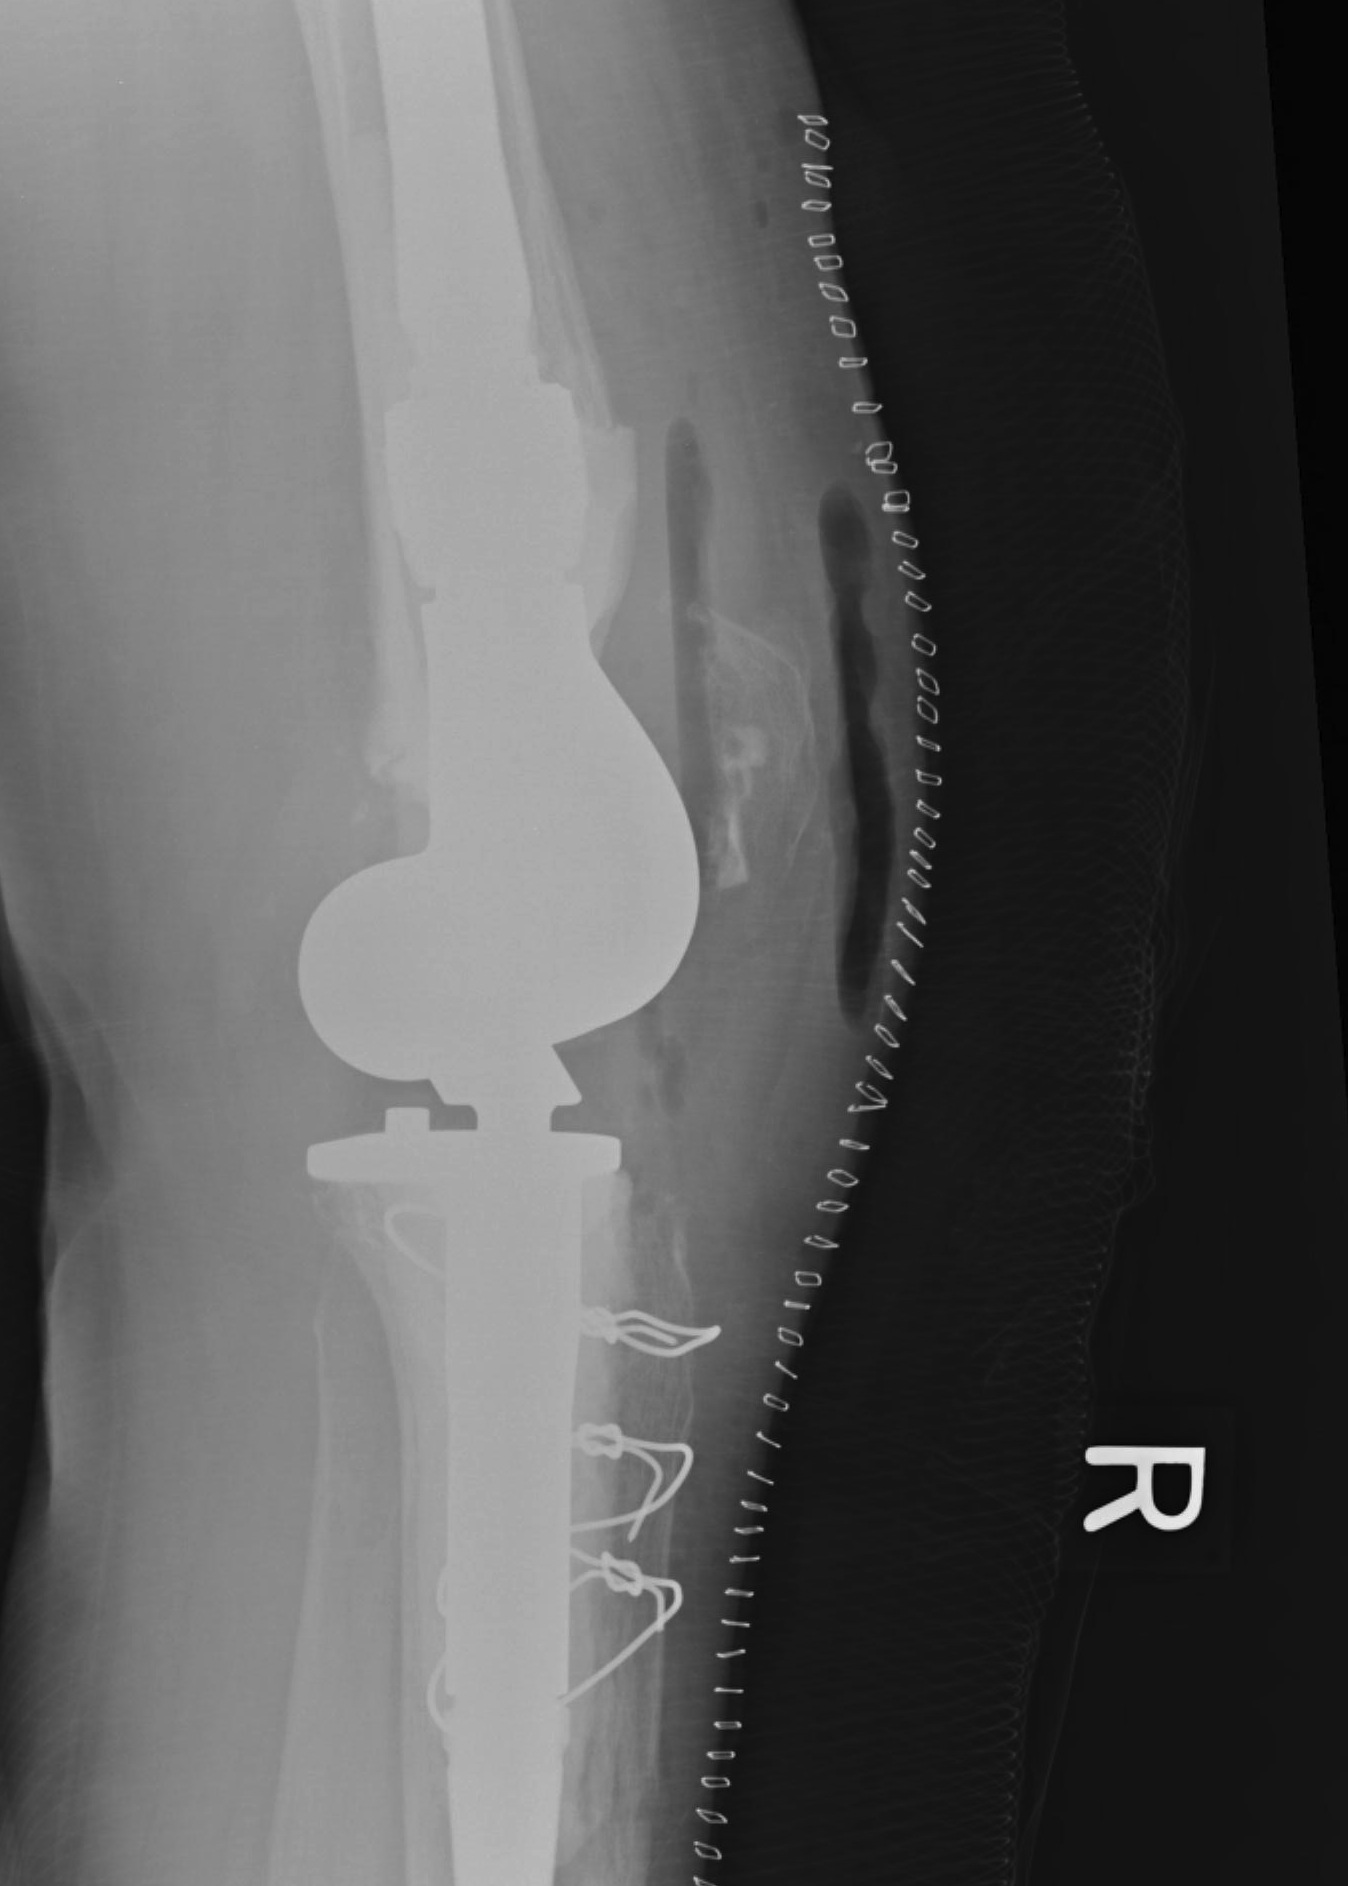

A. Bulk structural allograft

- femoral head

Engh et al JBJS Am 2007

- bulk structure allograft in the tibia in 46 patients followed for 8 years

- 2 deep infections

- average knee society scores 84

- no graft collapse or loosening